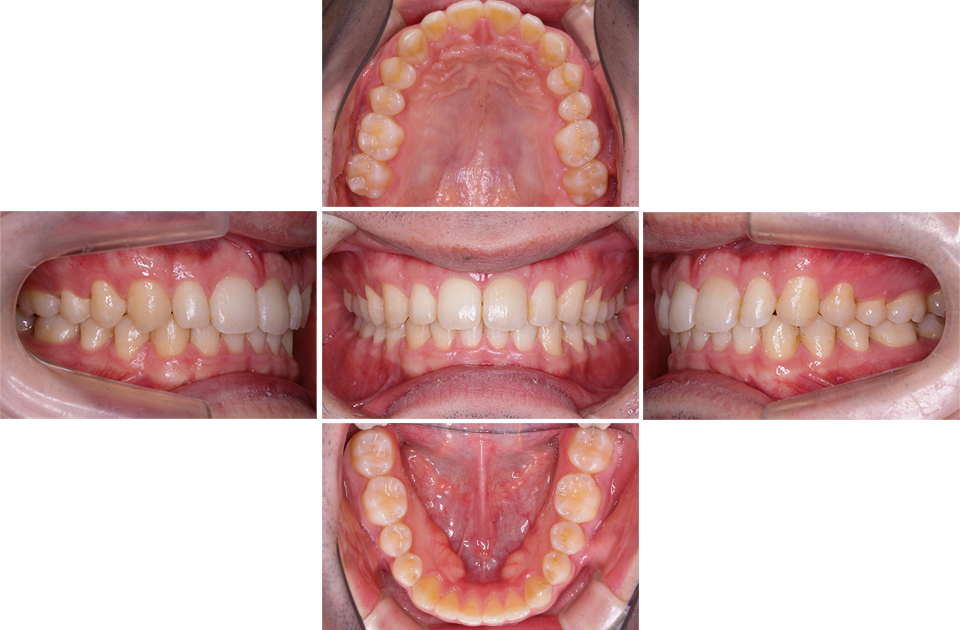

矯正前

矯正前 上顎

矯正前 下顎

主訴 正中が開いている。咬み合わせが深く歯肉を咬んでしまう。

年齢 20代

治療法 上下顎マルチブラケット装置

抜歯の有無 なし

治療期間 1年6ヶ月